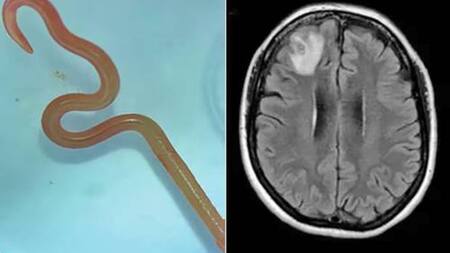

La extraña criatura que se retorcía era una larva de un gusano redondo autóctono de Australia, llamado Ophidascaris robertsi.

La cirujana Hari Priya Bandi fue partícipe de una situación inimaginable. Su paciente presentaba unos misteriosos síntomas que obligaron a la especialista a realizar una biopsia para dar con el problema. Cuando las pinzas atravesaron el pequeño agujero, se topó con un gusano de 8 centímetros de largo.

“Pensé: ‘¿Qué es esto? No tiene ningún sentido. Pero está vivo y se mueve’”, declaró Bandi. “Continuó moviéndose con vigor. Todos nos sentimos un poco asqueados”, añadió la neurocirujana al ser consultada sobre la situación que vivió.

“De repente, con sus pinzas (las de Bandi), está cogiendo esta cosa que se retuerce. Ella y todos los presentes en el quirófano se quedaron absolutamente atónitos”, agregó Senanayake.